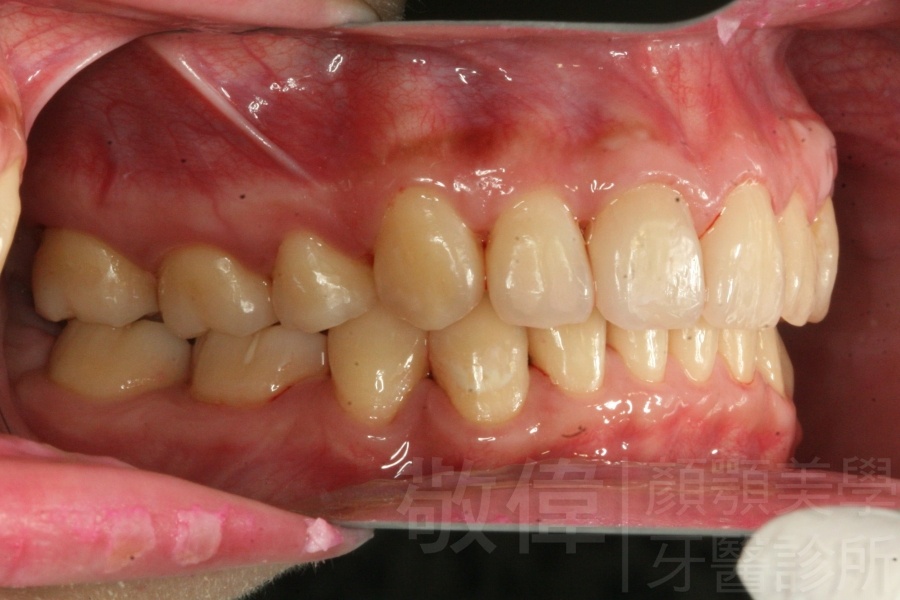

齒顏矯正/戽斗臉型 變身 大帥哥

矯正前-右   矯正前-正   矯正前-左

矯正後-右   矯正後-正   矯正後-左

矯正前-上   矯正前-下

矯正後-上   矯正後-下

<個案說明>

戽斗(學名第三級咬合 class III)矯正之後,戽斗的樣子就比較沒有了。最主要的改變是在牙齒的咬合。從側面比較,治療前、治療後的臉型 可更明顯看出來 戽斗的感覺 減少了很多。